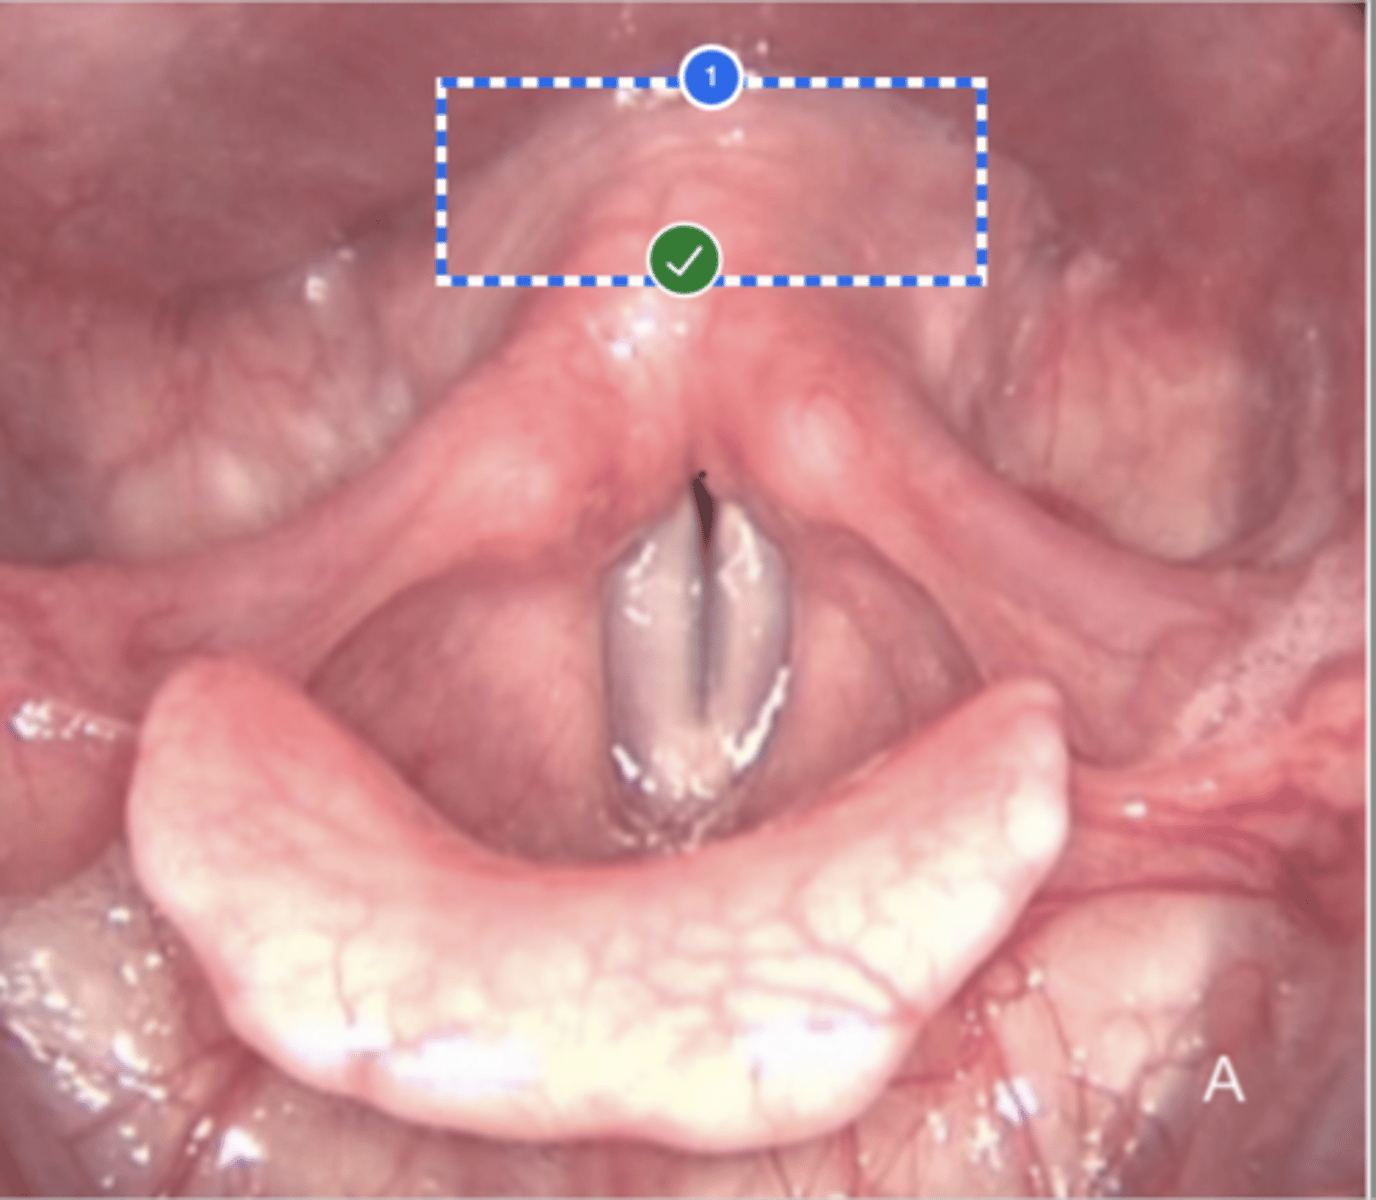

Label left true vocal fold (superior view)

Label right false vocal fold (superior view)

label right arytenoid (superior view)

Label trachea (superior view)

Label epiglottis (superior view)

Label left aryepiglottic fold (superior view)

Label laryngral surface of epiglottis (superior view)

Label lingual surface of epiglottis (superior view)

Label base of tongue (superior view)

Label right pyriform sinus (superior view)

Label upper esophageal sphincter (superior view)

Label right true vf (superior view)